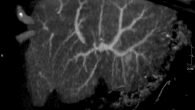

- сдать анализы и пройти обследования на печеночную и почечную функцию, свертываемость, состояние кровеносных сосудов, питающих опухоль (ангиограмма);

Процедура проводится в операционной специалистом по рентгено- и радиохирургии. Чаще лечение — амбулаторное, но может потребоваться кратковременная госпитализация. На основании полученной информации по ангиограмме вводится тонкая проволочная стека для защиты желудка и 12-перстного отростка кишечника от попадания микрочастиц с изотопом. Затем через кожный надрез в бедренную артерию вставляется катетер, через который (после достижения печеночных артерий) в кровоток запускаются меченные индикатором микросферы. Процесс осуществляется под контролем рентген-аппарата. В течение 1,5—2 недель после манипуляции радиочастички будут испускать в опухоль рассчитанную дозу излучения.